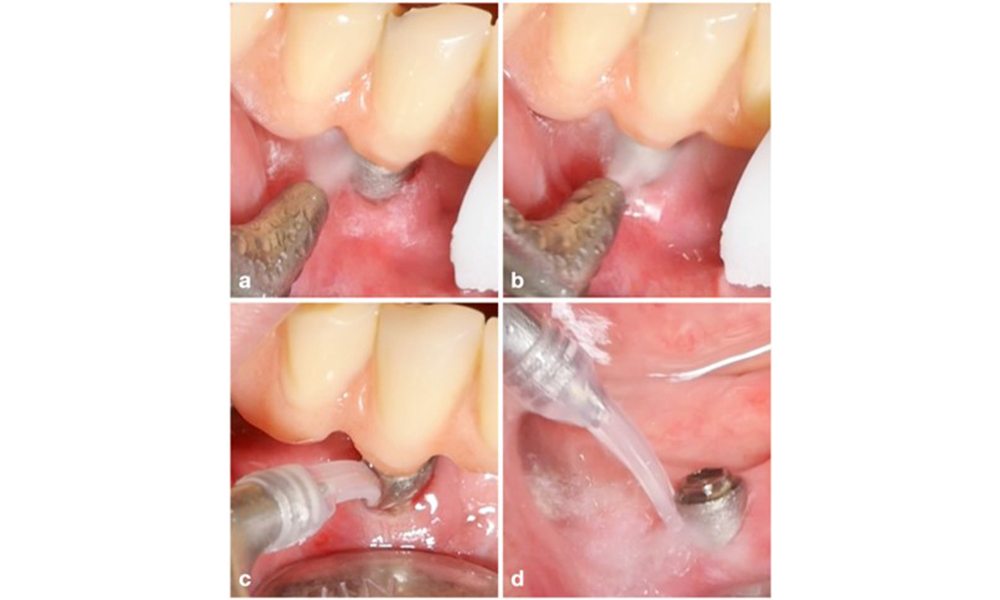

Patientenfall mit periimplantärer Mukositis, mangelnder Oralhygiene und Zahnstein (a). In einem solchen Fall ist eine Kombination unterschiedlicher Geräte ratsam. Beispielsweise sind Ultraschallscaler mit speziell geformter Spitze zum Entfernen des Zahnsteins erforderlich (b), während der restliche weiche Biofilm mit einem Luftpoliergerät entfernt werden kann (c-d).

Abb. 7. Patientenfall mit periimplantärer Mukositis, mangelnder Oralhygiene und Zahnstein (a). In einem solchen Fall ist eine Kombination unterschiedlicher Geräte ratsam. Beispielsweise sind Ultraschallscaler mit speziell geformter Spitze zum Entfernen des Zahnsteins erforderlich (b), während der restliche weiche Biofilm mit einem Luftpoliergerät entfernt werden kann (c-d).